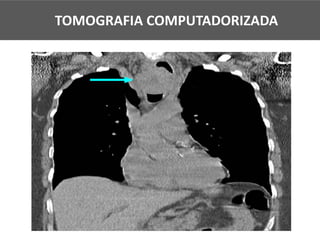

TOMOGRAFIA COMPUTADORIZADA